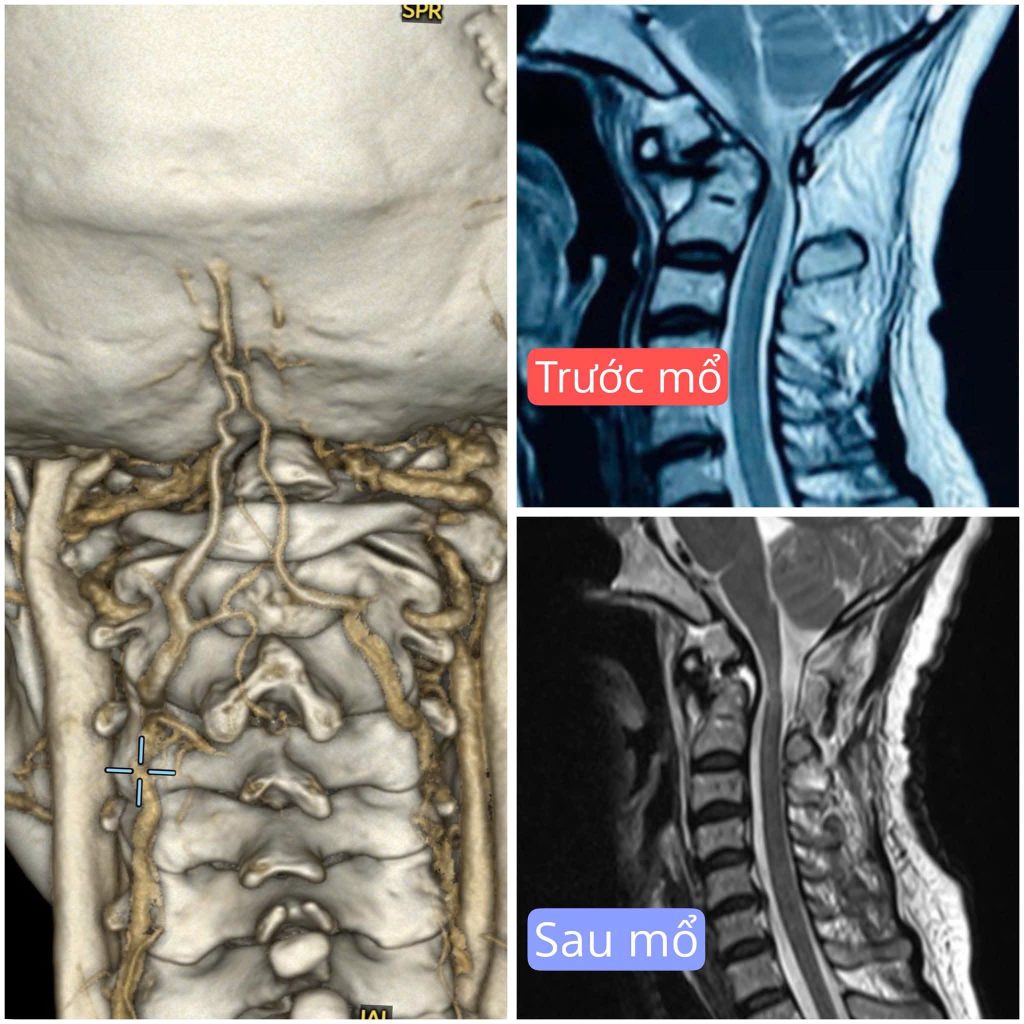

Tại phòng khám ngoại thần kinh, qua kết quả thăm khám và chụp MRI, bác sĩ Trần Vũ Hoàng Dương chẩn đoán chị Y. bị trượt đốt sống cổ C1 – C2, dẫn đến tình trạng mất vững cột sống cổ, đồng thời chèn ép tủy sống – nguyên nhân gây ra các triệu chứng như tê dị cảm tứ chi, mất vững cột sống, yếu nửa người phía bên trái.

Hình ảnh MRI trước vào sau phẫu thuật trượt đốt sống cổ

Thông thường, mỏm nha của đốt sống sẽ liền với thân đốt sống. Nhưng trường hợp của bệnh nhân Y., qua thám sát, các bác sĩ nhận thấy mỏm nha của đốt sống C2 rời khỏi thân đốt sống. Chính vì thế, nó chèn vào trong phần tủy sống kèm với tình trạng trượt đốt sống khiến bệnh nhân bị tê yếu dây thần kinh vận động, dị cảm tứ chi.

Ê-kíp các bác sĩ khoa Sọ Não Cột Sống 2 đã thực hiện cố định đốt sống C1– C2 bằng hệ thống nẹp – vít chuyên dụng, đồng thời giải áp tủy nhằm loại bỏ nguy cơ tổn thương thần kinh. Sau 2 giờ tập trung cao độ, ca phẫu thuật hoàn tất trong sự nhẹ nhõm của cả ê-kíp.

Sau phẫu thuật, bệnh nhân hết đau nhức vùng đầu cổ, cải thiện sức cơ vận động, chấm dứt những cơn tê lan xuống tay chân, thị lực ổn định trở lại. Giờ đây, chị Y. đã có thể tự đi lại vững vàng, cơ thể nhẹ nhàng, không còn nỗi lo nguy hiểm rình rập sức khỏe.